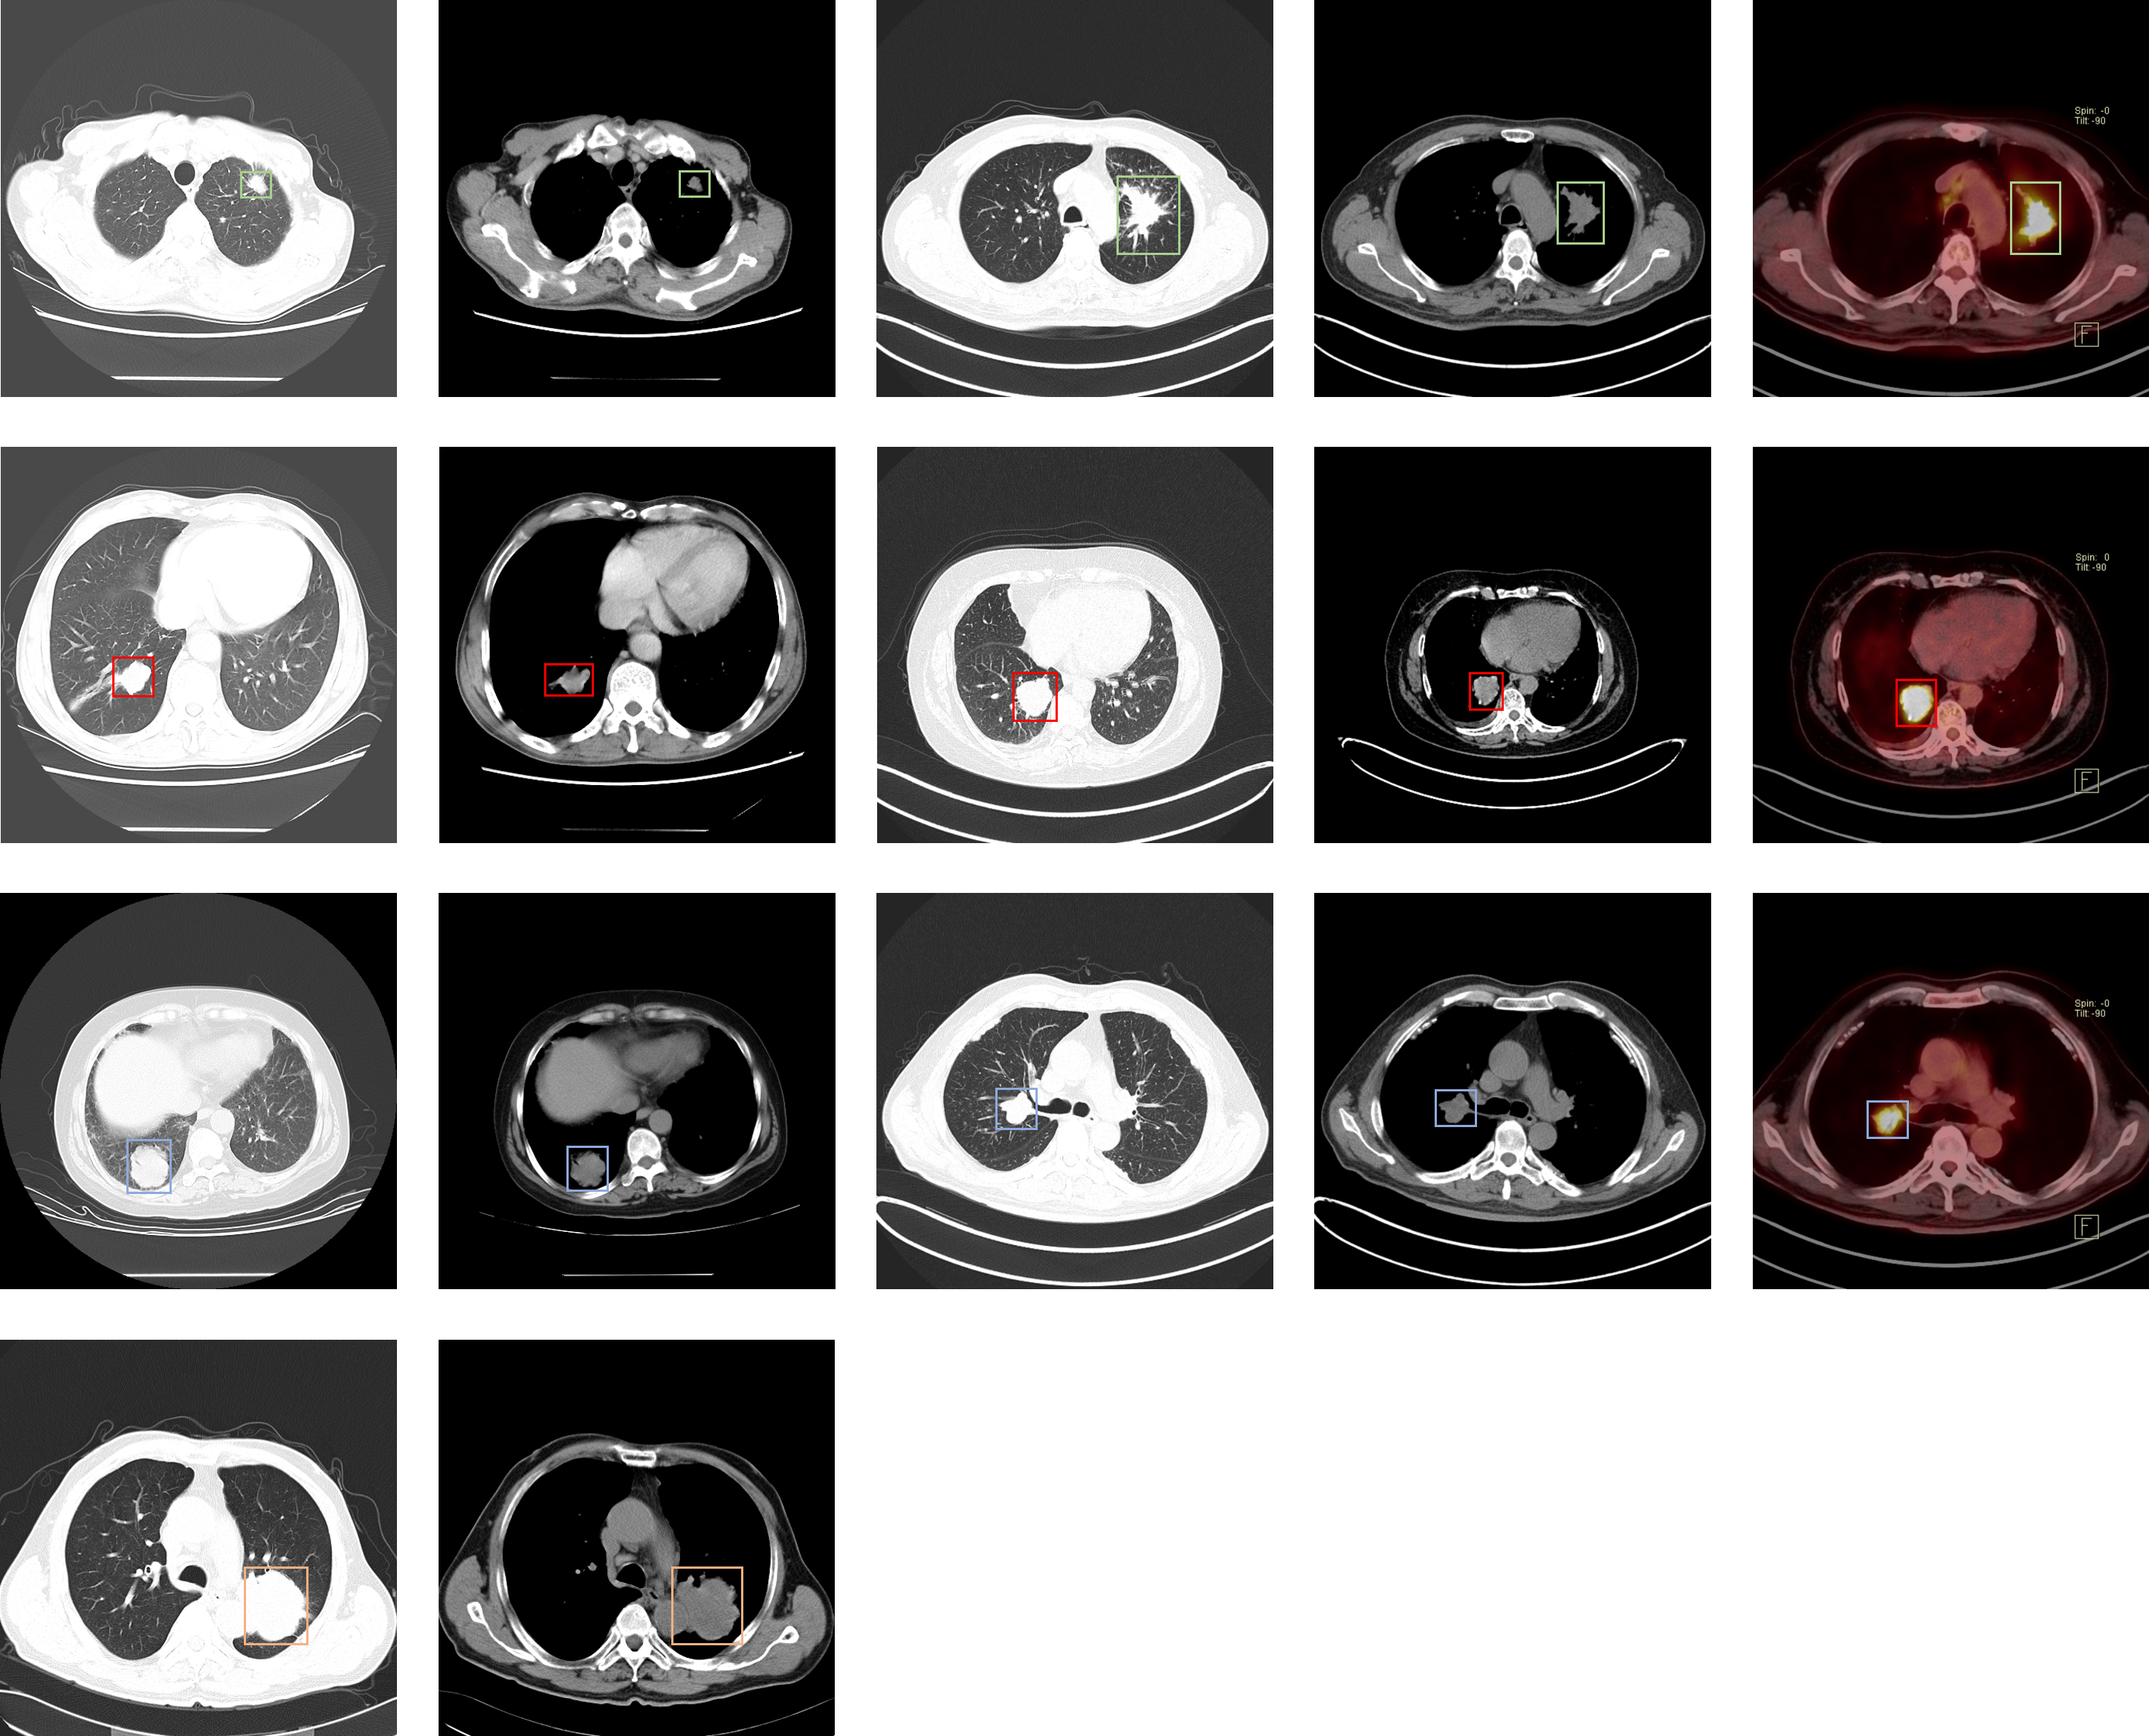

Lung-PET-CT-Dx

| Lung-PET-CT-Dx | 肺癌 | 目标检测 | CT | 363 | xml | dcm |

LIDC-IDRI

| LIDC-IDRI | 肺部肿瘤 | 目标检测 | CT | 1012 | xls | dcm |

LUNA16

NSCLC-Radiomics

| NSCLC-Radiomics | 非小细胞癌 | 分割 | CT | 422 | dcm |